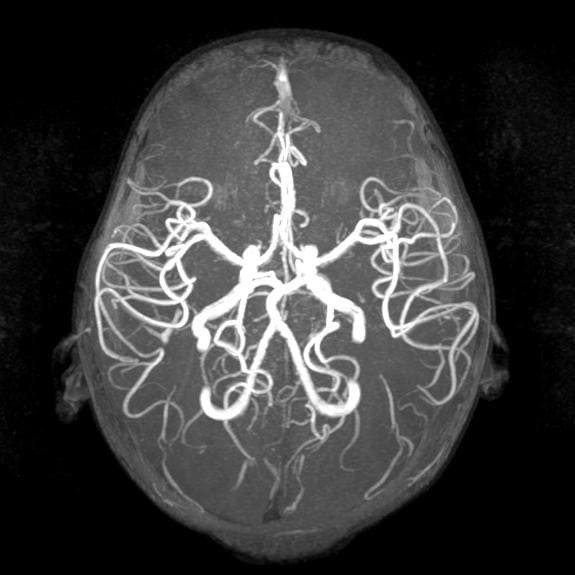

Если говорить о компьютерной томографии сосудов, то визуализация сосудов на КТ требует контрастирования на базе йода. Это обязательное условия, так как без контраста специалисты просто не увидят сосудистое русло.

Преимущество компьютерной томографии сосудов заключается в том, что она хорошо визуализирует аневризмы, и за короткий промежуток времени диагност может просканировать большой участок головной мог и шею, ноги или руки, аорту в брюшном, грудном отделе.

На КТ и МРТ ангиографии будут хорошо отображены даже мелкие артерии и вены. Это более детальная и точная форма диагностики. По своей информативности МРТ и КТ сопоставимы.

Зато КТ ангиография более быстрая форма сканирования. Томография сосудов на ней занимает всего 5-7 минут. МРТ сосудов в ангиорежиме длится около 20 минут.